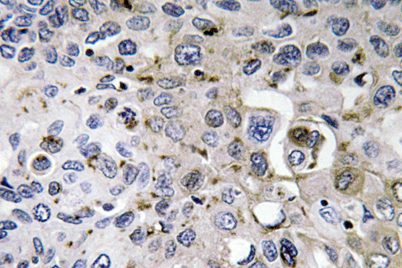

Product name: PDGF-A rabbit pAb

Dilutions: Western Blot: 1/500 - 1/2000. Immunohistochemistry: 1/100 - 1/300. ELISA: 1/40000. Not yet tested in other applications.